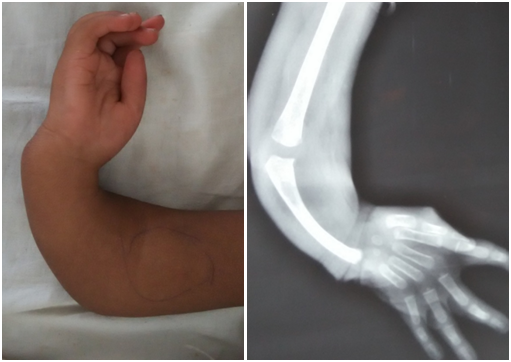

- Displasia radiale

- Paraliza obstetrikale